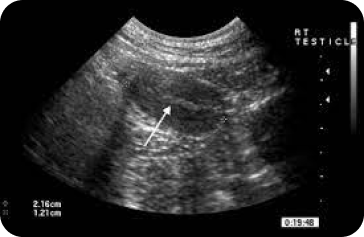

Testicles/ Scrotum

Precise examination to identify abnormalities or causes of pain, ensuring a clear diagnosis for appropriate care.